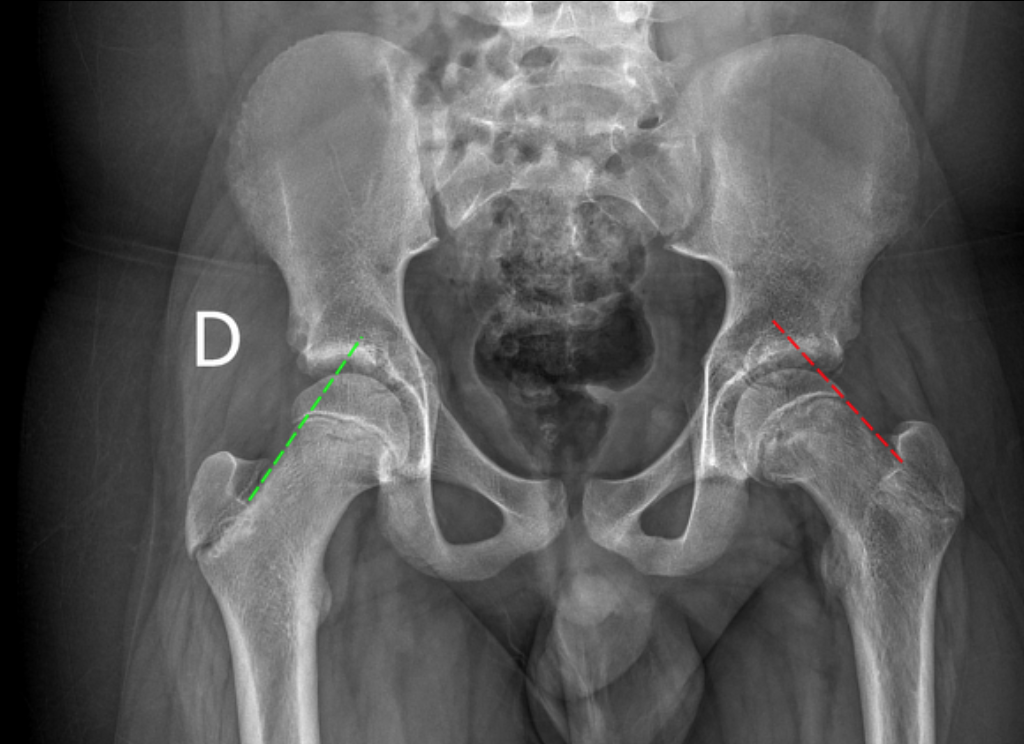

Slipped Capital Femoral Epiphysis

• Fat kids

• ~12 years old

• More often bilateral (30%)

• AA >caucasian

Klein Line

• Line drawn along superior edge of the femoral neck

• Should intersect the superior aspect of the femoral epiphysis

• If does not then concerning for SCFE